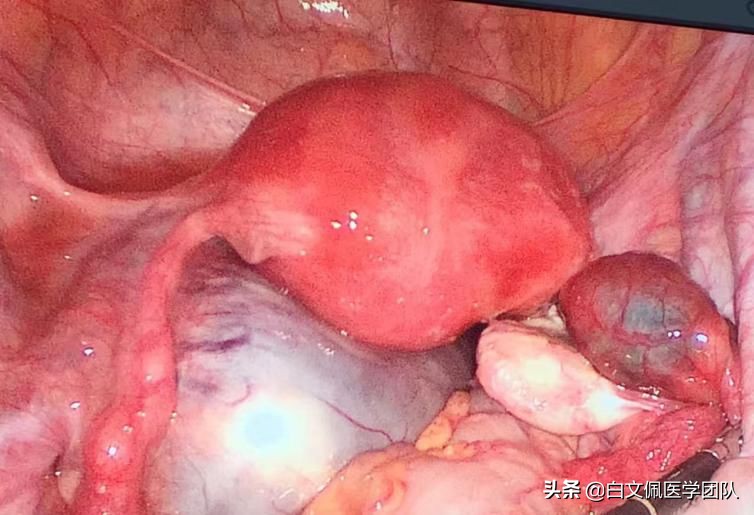

一、子宫峡部后壁的子宫肌瘤剔除

子宫峡部后壁的子宫肌瘤,直径10厘米,凸向右侧阔韧带,精心剔除并缝合,出血很少,保全子宫,皆大欢喜患者术后体温一直正常,一切顺利。